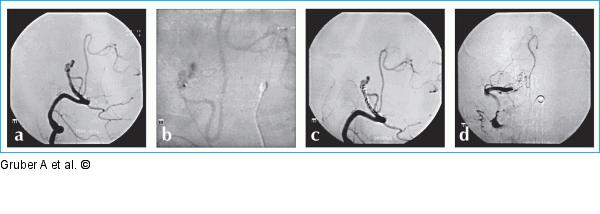

Abbildung 13a-d: "Flow modifiacation"-Technik "Flow modification"-Technik durch "Drosselung". Angiogramme der rechten A. vertebralis in seitlicher Projektion (a) sowie intraaneurysmale Mikroangiogramme (b) nach schwerer Subarachnoidalblutung zeigen ein rupturiertes Vertebralisaneurysma, welches den Abgang der rechten A. cerebelli inferior posterior inkorporiert. Durch partielle Coil-Embolisation der rechten Vertebralarterie in ihrem intraduralen Verlauf proximal des Aneurysmas (c) und gleichzeitiger Heparinisierung über 7 Tage kommt es zu einer langsam progredienten Thrombose dieses Segmentes der Vertebralarterie bei gleichzeitiger Entstehung suffizienter Kollateralkreislaufsysteme für die rechte A. cerebelli inferior posterior (d). |

Abbildung 13a-d: "Flow modifiacation"-Technik

"Flow modification"-Technik durch "Drosselung". Angiogramme der rechten A. vertebralis in seitlicher Projektion (a) sowie intraaneurysmale Mikroangiogramme (b) nach schwerer Subarachnoidalblutung zeigen ein rupturiertes Vertebralisaneurysma, welches den Abgang der rechten A. cerebelli inferior posterior inkorporiert. Durch partielle Coil-Embolisation der rechten Vertebralarterie in ihrem intraduralen Verlauf proximal des Aneurysmas (c) und gleichzeitiger Heparinisierung über 7 Tage kommt es zu einer langsam progredienten Thrombose dieses Segmentes der Vertebralarterie bei gleichzeitiger Entstehung suffizienter Kollateralkreislaufsysteme für die rechte A. cerebelli inferior posterior (d). |